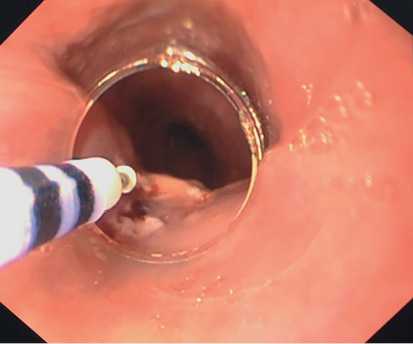

При помощи электрохирургического ножа DualKnife (Olympus, Япония) выполнена разметка границ по окружности новообразования (рис. 3). С помощью инъекционной иглы проксимальнее образования по заднеправой стенке пищевода сделана инъекция стерильного физиологического раствора, подкрашенного индигокармином, до образования плотного подслизистого инфильтрата.

Рис. 3. Разметка границ по окружности новообразования. Фото авторов.

Произведено рассечение слизистой оболочки пищевода по проксимальной полуокружности образования ножом DualKnife (режим Endo Cut Q Effect 3, ERBE VIO 300D) (рис. 4). Далее выполнена последовательная диссекция образования в подслизистом слое при помощи электрохирургического ножа DualKnife (режим Spray Coag Effect 2, ERBE VIO 300D).

Рис. 4. Рассечение слизистой оболочки пищевода. Фото авторов.